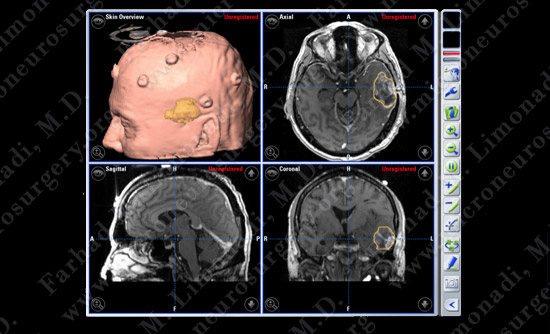

Computer navigation and stereotaxy utilized to map and localize the tumors (outlined in yellow) during surgery.